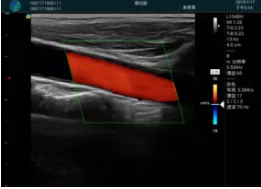

頸動脈血流充盈飽滿,無外溢